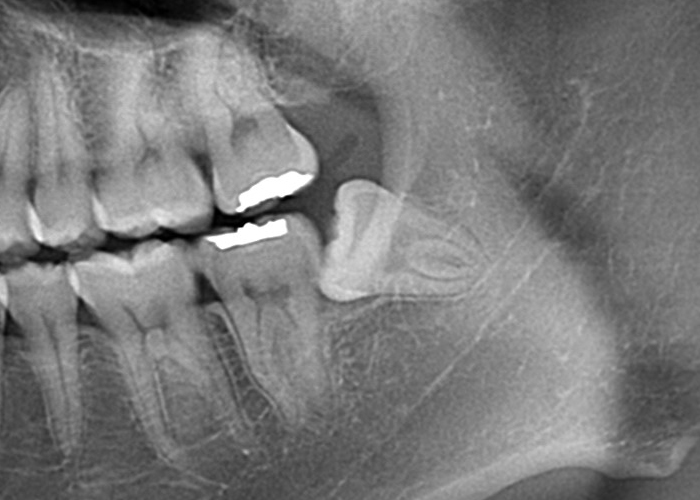

パノラマX線写真を撮影し親知らずの位置関係を把握します。

深さによってはCTまで撮影し3次元的な位置関係の把握を行います。その後局所麻酔と口腔内の清掃を行った上で抜歯します。

親知らずの頭や周囲の骨が引っかかって抜きづらい場合は親知らずを分割したり、周囲の骨を部分的に削除しながら親知らずの抜歯を行います。